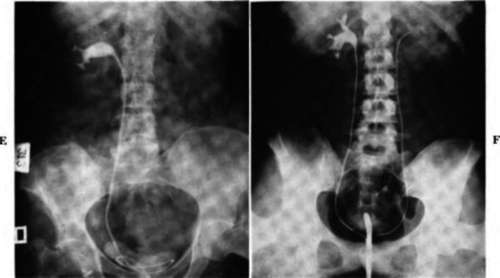

Fig. 77-cont'd. E, Right retrograde pyelograni showing a distortion of the calyces and an incomplete filling of all the calyces. The axis of the kidney is rotated. This was due to a renal cell carcinoma.

F, Right retrograde pyelograni showing a distortion of the lower calyceal group with irregularity and a loss of the normal calyceal outline. The infundibulum is widened. This is due to a cancer of the lower pole of the right kidney.